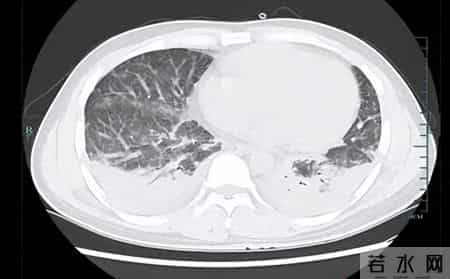

壮哥经检查:胸部CT双肺弥漫性病灶,血氧饱和度指标不到70%。“重症肺炎,I型呼吸衰竭。再拖下去有生命危险!”他随即被安排住院治疗,并做了基因检测,揪出了真凶——马尔尼菲篮状菌。

壮哥的肺部情况